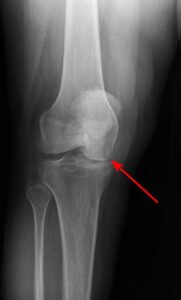

Understanding Ankle Fractures in Children

In children and adolescents, ankle fractures typically affect the tibia or fibula, often involving the growth plates—specialized areas of cartilage near the ends of long bones. Growth plates play a critical role in bone development, gradually hardening into solid bone as the child matures. However, because these growth plates are the last parts of the bones to solidify, they are particularly prone to injury and fractures.